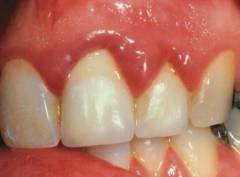

Здоровые десны имеют бледно-розовый цвет и плотно обвивают шейку зуба. Десневая ткань хорошо кровоснабжается за счет ветвей наружной сонной артерии. Иннервация осуществляется ветвями тройничного нерва — верхнечелюстным и нижнечелюстным нервами. Эти нервы образуют зубные сплетения, от которых отходят десневые и зубные ветви, регулирующие тонус сосудов и питание тканей. Десны содержат множество нервных окончаний, отвечающих за болевую и температурную чувствительность.

Гингивит — воспаление десны без повреждения зубодесневого соединения. Он может быть локализованным или генерализованным и чаще встречается у молодых людей. При легких формах воспаление затрагивает только межзубные сосочки, в тяжелых — всю десну.

Катаральный гингивит

Пациенты жалуются на дискомфорт, жжение и распирание в десне, усиливающиеся при приеме пищи. Наблюдаются припухлость и кровоточивость десен. Катаральный гингивит обратим и проходит при своевременном лечении.